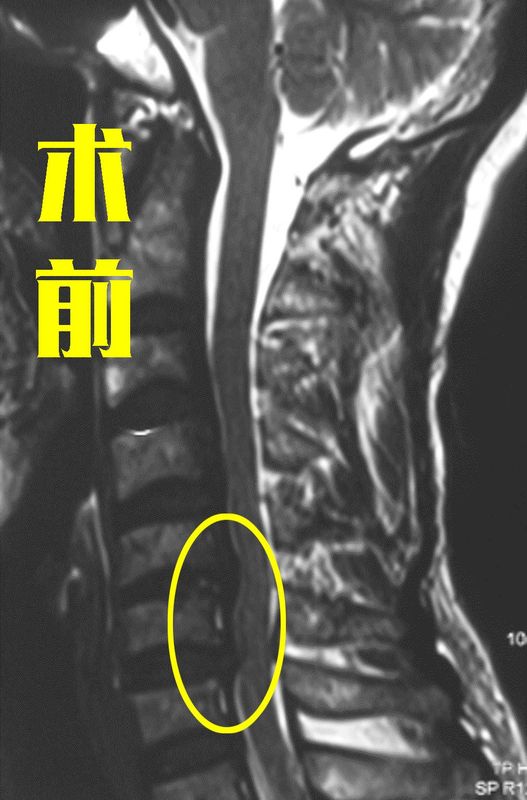

我们之前的文章里面给大家讲过,约10%左右的颈椎病患者治疗需要手术介入,这类手术常做有颈前路手术和颈后路手术。对于颈椎间盘突出症的患者来说,这两种手术各有优缺点,颈前路手术虽较为微创,但适用于2个节段以下的单纯颈椎间盘突出患者;而颈后路手术可以很好的解决病情复杂、多节段患者的问题,但是手术创伤相对大一点。那就有很多患者犯难了,“我的颈椎间盘突出是3个节段的,这该怎么选?还能做微创的颈前路吗?”最近,宣武医院王作伟主任门诊来了一位73岁的女性患者。她在4年前就出现了颈部疼痛、左胳膊疼麻的情况,当时去了当地医院就诊后就查出来有3个节段都出现了颈椎间盘突出,医生让她先保守治疗试试。治疗后,她的症状略有缓解,但之后又做了几次治疗后,效果不是太好。症状断断续续地发作,她就自己忍着,把这当成了老毛病。直到今年,她的疼痛加剧,还感到胳膊、腿没劲,严重影响到她的生活,比如不能正常吃饭拿筷子、穿衣服、走不稳等。随后,她的家人陪她又去了当地医院就诊,这次的建议是手术。年龄这么大了,要不是确实严重影响生活,他们本来不想手术的。后面在了解手术事宜时,家人发现她是多节段的突出,当地建议手术从颈后路做,但他们害怕对老人伤害太大,迟迟不敢下决心。最近,他们决定带老人到北京再看看,最后才找到了王主任。颈椎间盘突出了3个节段,手术还做颈前路吗?还是要看患者的具体情况。结合这位患者的片子,她在颈4-5、颈5-6、颈6-7三个节段都出现了明显的椎间盘突出,并且还造成颈椎管狭窄,神经、脊髓压迫严重,再加上她的症状严重影响生活质量,长期保守治疗无效,这个时候确实需要手术把她的这些病痛解除。术前影像学资料:那手术是选择颈前路还是颈后路呢?一般情况下,颈前路手术从自然间隙进入,对肌肉等软组织的损伤很小,术后患者恢复得也快,所以能做颈前路的话最好还是做颈前路。但如果患者的情况复杂,突出的节段也很多,这时颈前路就不能解决问题了,需要颈后路手术才能彻底解决问题,但术后有些患者可能由于手术剥离肌肉多,出现一段时间的颈部不适。那这位患者的情况是否适合做颈前路呢?其实,这位患者虽然年龄有点大,但是颈椎的条件是比较好的,再结合她的各项检查,王主任建议她可以做颈前路手术。做完3个节段的颈前路手术,效果真的好吗?患者和家属欣然同意手术方案后,由王主任亲自操刀,为她成功进行了颈前路的手术,术中切除突出的椎间盘,给神经、脊髓进行了彻底减压,颈椎管也恢复得通畅,并成功进行内固定。术后,患者的胳膊疼痛症状得到明显缓解,胳膊麻、肢体无力的情况也在减轻,效果非常明显。术后影像学资料:其实,患者在手术方面比较谨慎是可以理解的,建议大家去正规的大医院咨询经验丰富的医生。这些医生临床上遇到这类情况很多,会根据您的具体情况给出适合的方案,一般颈前路手术能解决问题的都会建议颈前路。